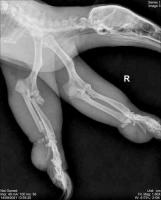

El oso hormiguero que fue atropellado en la carretera de la Riviera Veracruzana, sobrevivió a la cirugía para corregir las dos fracturas en uno de sus brazos, para lo cual se requirió colocar clavos externos porque no se cuenta en México con placas del tamaño de este animal de la vida silvestre.